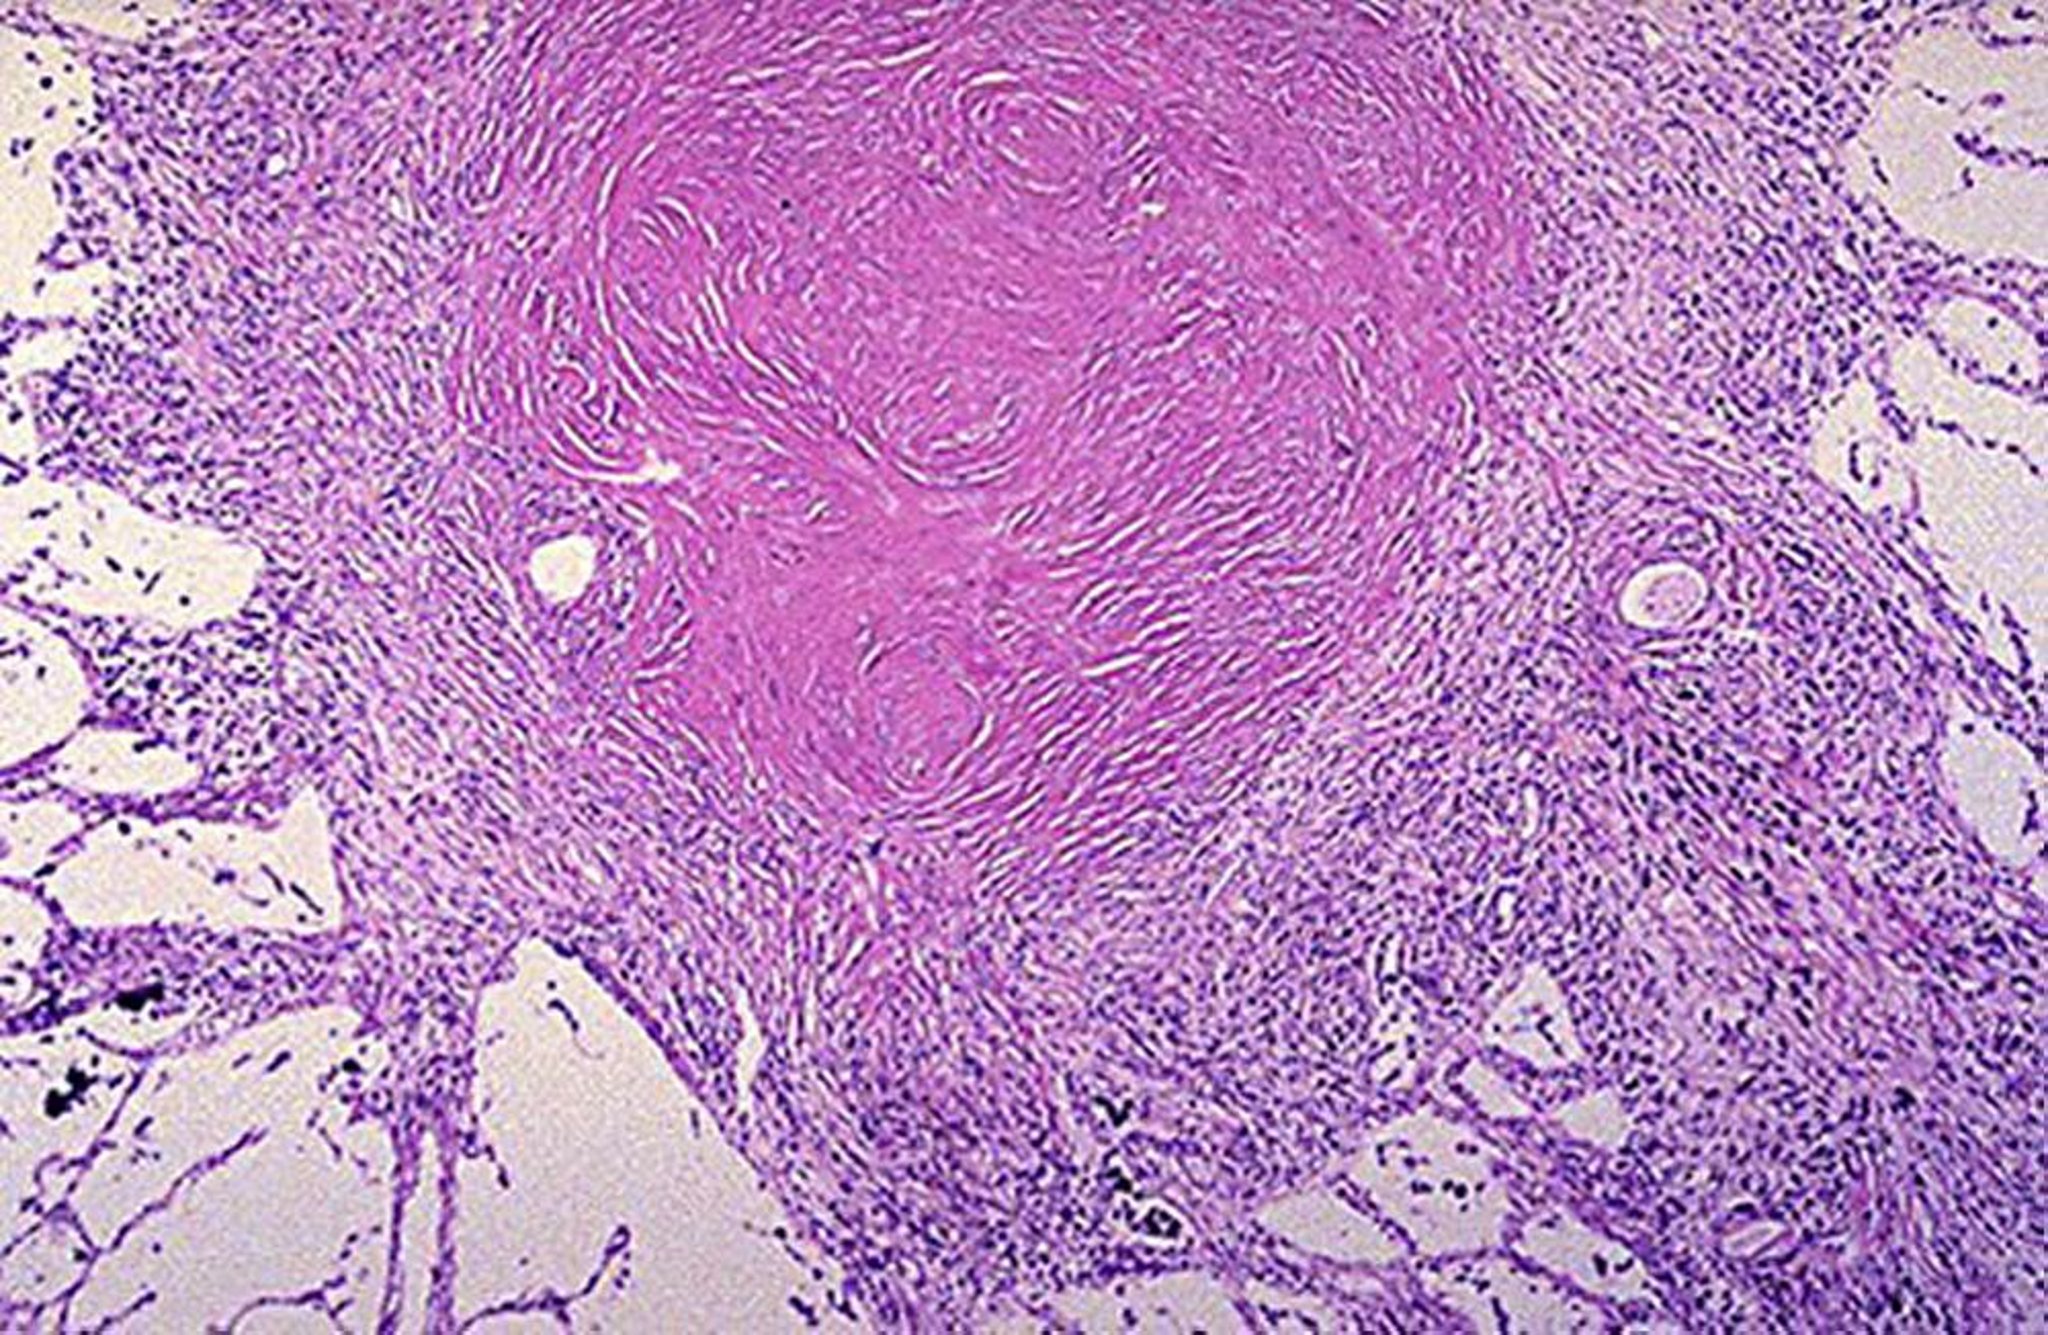

Nodulo silicotico

Image courtesy of David W. Cugell, MD.